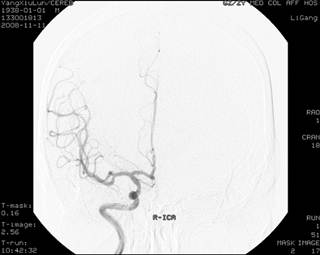

In October 2008, a 50-year-old man presented with progressive fever, headache, nausea and vomiting for five days. On physical examination, the temperature was 39 ℃, blood pressure (BP) was 86/60 mm Hg, bulbar conjunctiva was congestive. But his neurological system and other systemic examinations were unremarkable. His white blood cell was 23×109/L, haemoglobin was 166g/L, blood platelet was 79×109/L, urea was 16.85 mmol/L, creatinine was 291 umol/L and uric acid was 496 umol/L. The results of prothrombin time (PT), activate part blood coagulation time (APTT), thrombin time (TT) and fibrinogen (FIG) were in normal range. Both hepatitis B and C virus test were negative. Cerebral computed tomography (CT) scan was normal (Fig. 1). The electroencephalogram showed slight abnormality, and both intracranial pressure and cerebrospinal fluid were normal. The patient was diagnosed and treated as viral encephalitis. However, seven days later, his headache became more and more serious and the second cerebral CT presented SAH (Fig. 2), but there was no remarkable finding on neurological examination. The next day, he presented neck rigidity. Therefore, intracranial vascular digital subtraction angiography (DSA) was carried out to find out the cause of SAH. However, the result of DSA was unremarkable (Fig. 3A and B). In order to find out the pathogen, we consulted a doctor for infectious diseases; she considered it to be EHF and suggested us to detect the serum antibody EHF-IgM and EHF-IgG, and both results were positive by indirect immunofluorescence in our central laboratory.

Figure 3

DSA showed unremarkable in the bilateral internal carotid artery (ICA) (A: right, B: left)

EHF caused by hantavirus is a severe systemic infection, with acute shock, vascular leakage, hypotension, and acute renal failure. Its clinical courses are divided into five phases: febrile, hypotensive, oliguric, diuretic and convalescent1,2,8. Hantavirus EHF with renal syndrome could be found in most region of China. Another haemorrhagic fever caused by dengue virus with renal syndrome is found mainly in the south of China9. Cases of the performance of nervous system damage after EHF were sporadically reported. And this case was to report, for the first time, the SAH associated with the EHF. As is known to all, the causes of SAH are intracranial aneurysm and intracranial vascular malformations or agenesis10,11. Clinically, patients with suspected SAH could be diagnosed by the head CT or lumbar puncture, and DSA is the most effective way to find out the causes of SAH. But there is no abnormal condition in the DSA in our patient. Diagnosis of EHF is mainly based on the smptoms and a history of exposure to the endemic focus area where Zunyi is an epidemic area of EHF. Moreover, this patient presented with positive hantavirus-IgM and IgG, and his clinical process was representative. The whole appearance is like EHF followed by SAH, although the familiar bleeding part of EHF is not in the subarachnoid space2.